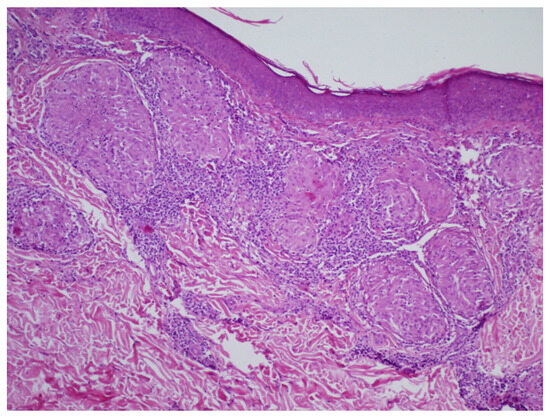

3.2. Diagnosis of Cutaneous Sarcoidosis